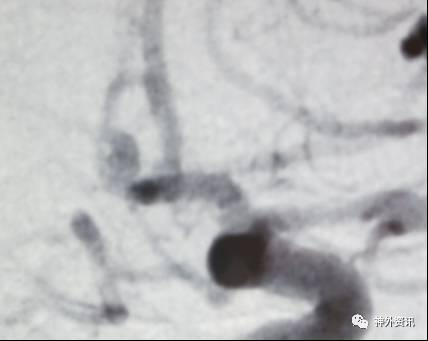

微导管成袢技巧

适用于:

(1)颈内动脉-眼动脉段的Carotid Cave动脉瘤

(2)大脑前动脉A1起始段的偏下方指向动脉瘤

(3)其他载瘤动脉近心端走行方向与动脉瘤指向之间大于90度的微导管到位

注意事项:

(1)上述动脉瘤指向的成角过大,即使使用微导丝进入动脉瘤囊内导引,微导管顺行到位也难以实现

(2)成袢的微导管常常弹跳进入动脉瘤囊内,有动脉瘤破裂风险

塑型要点:

(1)基于载瘤动脉走向与动脉瘤指向的微导管塑型,并适当增加微导管头端的直行长度,有助于成袢和微导管稳定性

(2)可利用颈内动脉分叉或大脑中动脉M1分叉进行微导管成袢

眼动脉动脉瘤,支架完全释放后,微导管成袢逆行到位

眼动脉动脉瘤,支架释放前,微导管成袢逆行到位

A1起始段动脉瘤,微导管成袢逆行到位